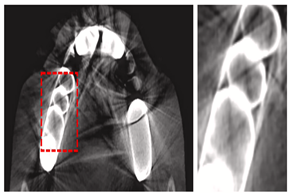

4.3.2. Extraoral X-Rays Images

Extraoral X-ray images are diagnostic tools used to capture detailed views of the teeth, jaw, and facial structures from outside the mouth, aiding in comprehensive dental assessment and treatment planning. Dentists use various extraoral X-rays, such as Panoramic X-rays, Cephalometric Projections (CP), and Cone-beam Computed Tomography (CBCT). These imaging techniques provide comprehensive views of dental structures, aiding in accurate diagnosis and effective treatment planning. Panoramic X-rays offer a wide view of the jaw and teeth, while CP focuses on the skull and jaw relationships offer insights into the relationships between the jaw and skull, crucial for orthodontic planning. In addition, AI in 3D dental imaging enhances diagnostics and treatment planning by analyzing CBCT scans to accurately identify issues like cavities and fractures. CBCT stands out by providing high-resolution 3D images, allowing for precise diagnosis and treatment planning, particularly in complex cases like implants and orthodontics. These 3D images provide a detailed view of dental structures, aiding in the creation of precise treatment plans for implants and orthodontics by simulating scenarios and predicting outcomes. These advancements in 3D imaging enhance the dentist’s ability to accurately identify and address dental issues, ultimately improving patient outcomes. Automated measurements and AI-generated models improve efficiency and patient communication, while predictive analytics aid in informed decision-making. CBCT provides detailed 3D images, crucial for complex procedures like implants and orthodontics, ensuring precise assessments and interventions.

| Cone-beam Computed Tomography (CBCT) | [19,38,53,64,67,93,97,98,99,100,101,102,103,104] | Endodontics, orthodontics, implant, oral surgery, and oral medicine | ![]() | High resolution 3D volumetric data. |